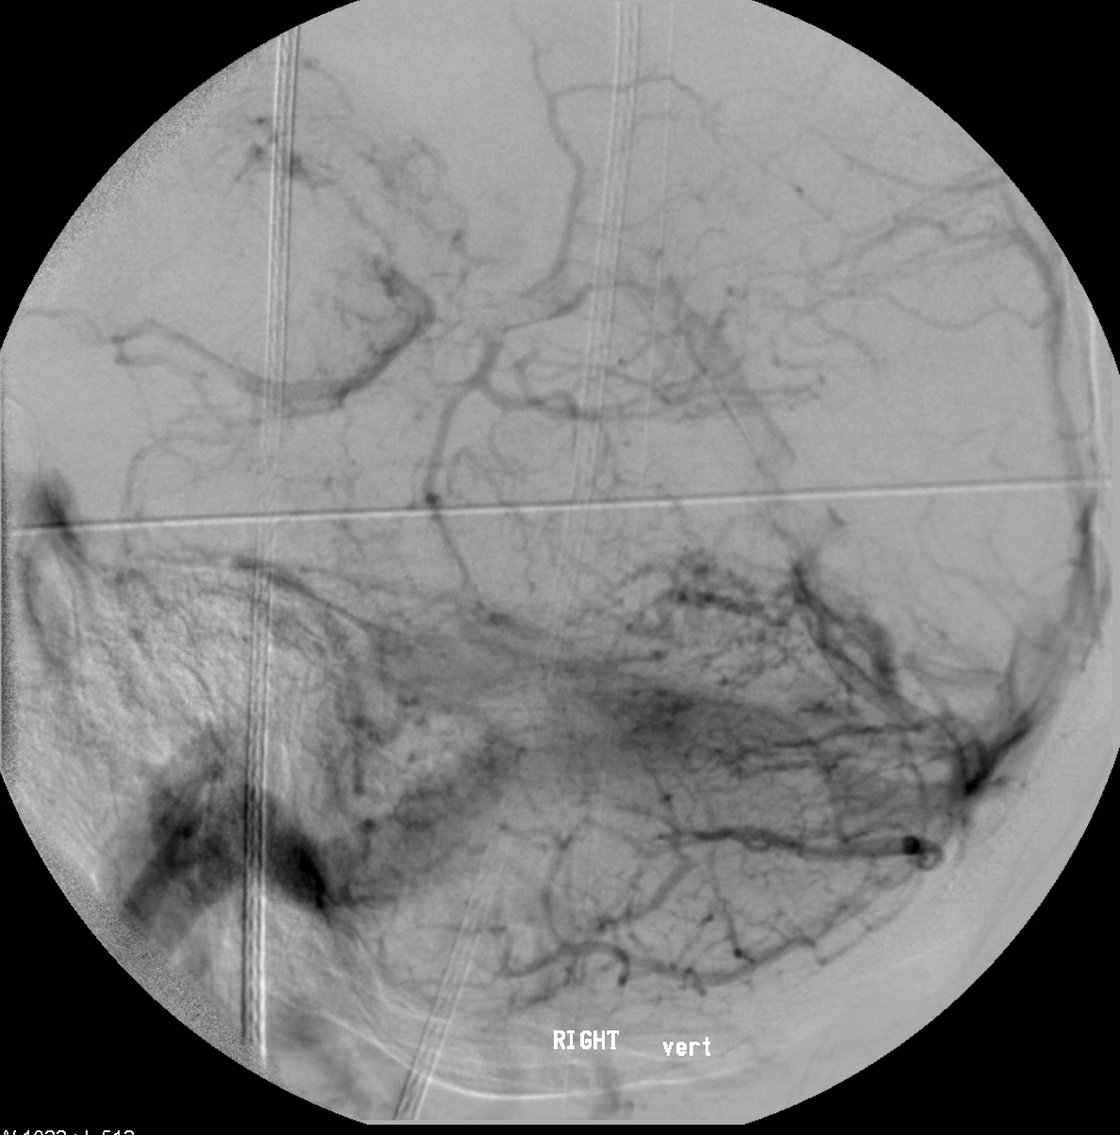

Indirekte A. carotis - Sinus cavernosus Fistel - Präinterventionell

Selektive Darstellung der A. carotis interna und externa. Es zeigt sich die deutlich verfrühte Füllung des Sinus cavernosus mit Abstrom über die dilatierte V. ophthalmica.